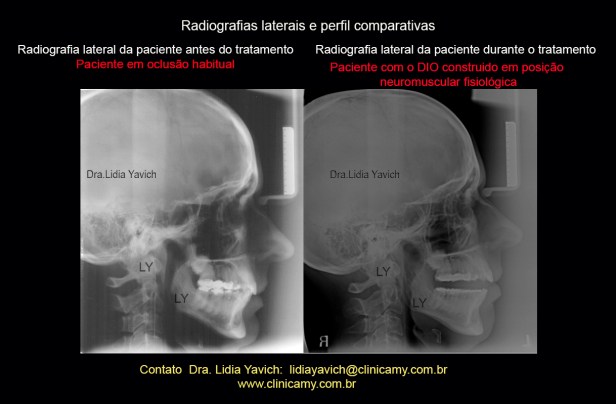

Comparação das radiografias laterais do paciente: em oclusão habitual antes do tratamento e com o DIO (dispositivo intraoral), em posição neuromuscular fisiológica.

Comparação das radiografias laterais do paciente: em oclusão habitual antes do tratamento e com o DIO (dispositivo intraoral), em posição neuromuscular fisiológica.

Melhora do perfil e recuperação da dimensão vertical.